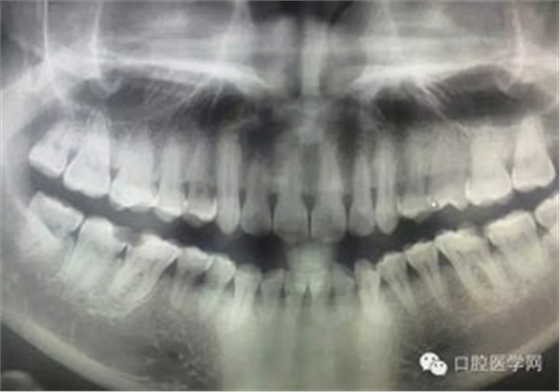

病例1:患者迫切希望保留自己的這一顆牙齒,根尖周陰影比較大,二度松動(dòng).而且旁邊有種植修復(fù)體,和患者溝通好后,治療好后觀察一個(gè)月后冠修復(fù),因?yàn)橛蟹N植的后期修復(fù),所以有了機(jī)會(huì)觀察,術(shù)后三個(gè)月和術(shù)后四個(gè)月,根尖恢復(fù)的還算不錯(cuò),希望能夠繼續(xù)觀察下去.這樣子的病例,做的時(shí)候我們一定要非常的小心,和患者要有充分的溝通以及不同科室的溝通然后決定怎么樣做比較好,假如就是出現(xiàn)了問題,到時(shí)候我們也比較好處理些,免得我們自己到時(shí)候不好收?qǐng)觥?/span> 病例2:364647中齲的樹脂充填,現(xiàn)在樹脂的充填材料非常之多,有些時(shí)候,我們感覺有了好的材料我們就可以做出好的修復(fù),可是這是在我們有扎實(shí)的基本功的基礎(chǔ)上的,我們可以沒有那么好的樹脂,那么多的顏色選擇,修復(fù)的那么的逼真,但是我們至少要恢復(fù)患者牙齒的功能,將腐質(zhì)去除干凈,薄壁弱尖消除掉,選擇好適應(yīng)癥,給患者以盡可能好的修復(fù)。 來源于KQ88